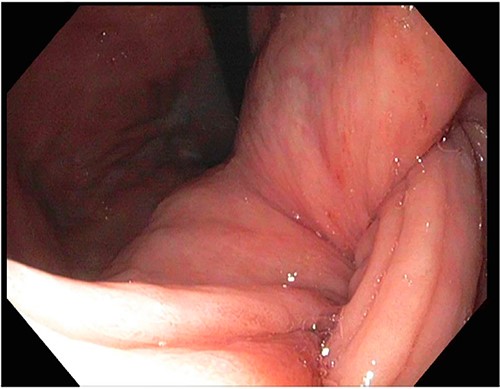

After a few days, the patient was found to have a large volume of melenic stool. A CT angiogram of the chest, abdomen and pelvis was done, revealing a mass in the antrum and pylorus of the stomach with a portion of the stomach pulled into it, consistent with gastroduodenal intussusception without any active extravasation. Repeat EGD showed a large, fungating, pedunculated mass with no bleeding and no stigmata of recent bleeding in the gastric body (Figs. 3 and4) and confirmed gastroduodenal intussusception. The intussusception spontaneously reduced while attempting to push passed the mass. The mass was too large to resect endoscopically. Given these new findings, the family agreed to surgical intervention. An exploratory laparotomy was made, and the patient underwent partial gastrectomy, distal antrectomy and Billroth II procedure. The resected large gastric body mass within the mid gastric body and two nodes were sent for frozen section and immunohistochemical analysis. The pathology report confirmed the mass as a GIST, spindle cell type with no significant nuclear atypia or mitosis, arising from muscularis propria, without mucosal invasion and R0 margins. The neoplastic cells stained positive for CD117 (KIT), CD34 and Desmin (focally). The tumor was T3N0M0 with a low mitotic rate, histologic grade G1 and was deemed low risk (3.6%). The patient was discharged to a subacute rehab with an uneventful recovery.